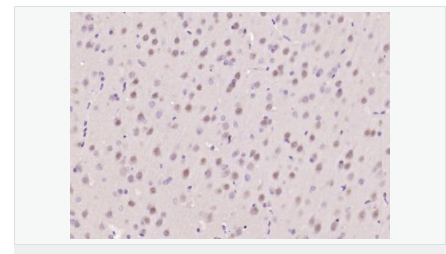

| 產(chǎn)品應(yīng)用 | WB=1:500-2000 ELISA=1:5000-10000 IHC-P=1:100-500 IHC-F=1:100-500 Flow-Cyt=1μg /test IF=1:100-500 (石蠟切片需做抗原修復(fù)) not yet tested in other applications. optimal dilutions/concentrations should be determined by the end user. |

| 細(xì)胞定位 | 細(xì)胞核 細(xì)胞漿 |

| 產(chǎn)品介紹 | ATF6 is a transcription factor that acts during endoplasmic reticulum stress by activating unfolded protein response target genes. It binds DNA on the 5'-CCAC[GA]-3'half of the ER stress response element (ERSE) (5'-CCAAT-N(9)-CCAC[GA]-3') and of ERSE II (5'-ATTGG-N-CCACG-3'). Binding to ERSE requires binding of NF-Y to ERSE. ATF6 could also be involved in activation of transcription by the serum response factor. ATF6 exists as a homodimer and heterodimer with ATF6 beta. The dimer interacts with the nuclear transcription factor Y (NF-Y) trimer through direct binding to NF-Y subunit C (NF-YC). It also interacts with the transcription factors GTF2I, YY1 and SRF. Under ER stress the cleaved N-terminal cytoplasmic domain translocates into the nucleus. The basic domain of ATF6 functions as a nuclear localization signal and the basic leucine zipper domain is sufficient for association with the NF-Y trimer and binding to ERSE. During the unfolded protein response an approximately 50 kDa fragment containing the cytoplasmic transcription factor domain is released by proteolysis. The cleavage seems to be performed sequentially by site 1 and site 2 proteases. ATF6 is N glycosylated, phosphorylated in vitro by MAPK14/P38MAPK and belongs to the bZIP family. Function: Transcription factor that acts during endoplasmic reticulum stress by activating unfolded protein response target genes. Binds DNA on the 5'-CCAC[GA]-3'half of the ER stress response element (ERSE) (5'-CCAAT-N(9)-CCAC[GA]-3') and of ERSE II (5'-ATTGG-N-CCACG-3'). Binding to ERSE requires binding of NF-Y to ERSE. Could also be involved in activation of transcription by the serum response factor. Subunit: Homodimer and heterodimer with ATF6-beta. The dimer interacts with the nuclear transcription factor Y (NF-Y) trimer through direct binding to NF-Y subunit C (NF-YC). Interacts also with the transcription factors GTF2I, YY1 and SRF. Subcellular Location: Endoplasmic reticulum membrane; Single-pass type II membrane protein. Processed cyclic AMP-dependent transcription factor ATF-6 alpha: Nucleus. Note=Under ER stress the cleaved N-terminal cytoplasmic domain translocates into the nucleus. Tissue Specificity: Ubiquitous. Post-translational modifications: During unfolded protein response an approximative 50 kDa fragment containing the cytoplasmic transcription factor domain is released by proteolysis. The cleavage seems to be performed sequentially by site-1 and site-2 proteases. N-glycosylated. The glycosylation status may serve as a sensor for ER homeostasis, resulting in ATF6 activation to trigger the unfolded protein response (UPR). Phosphorylated in vitro by MAPK14/P38MAPK. Similarity: Belongs to the bZIP family. ATF subfamily. Contains 1 bZIP (basic-leucine zipper) domain. SWISS: P18850 Gene ID: 22926 Database links: Entrez Gene: 22926 Human Entrez Gene: 226641 Mouse Omim: 605537 Human SwissProt: P18850 Human Unigene: 492740 Human Important Note: This product as supplied is intended for research use only, not for use in human, therapeutic or diagnostic applications. |